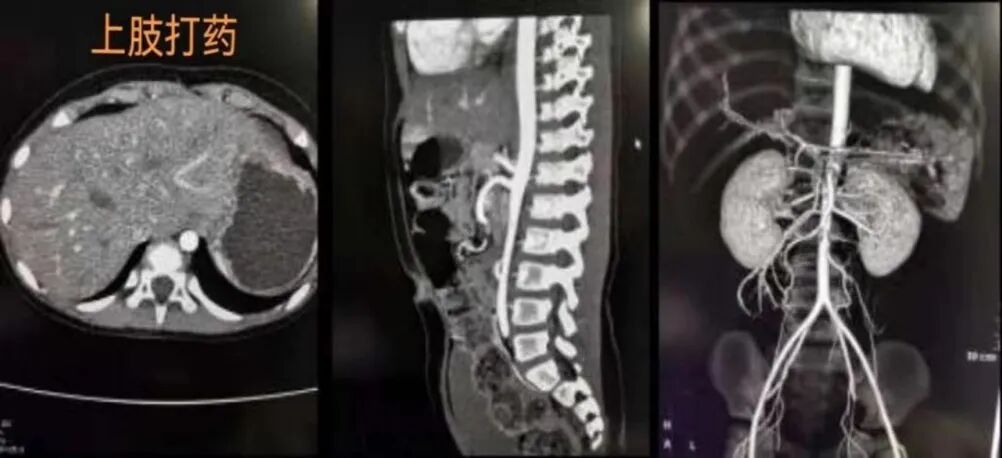

以下,我们就以图为例了解一下团注造影剂分别从右侧上肢及左侧上肢进入到人体内进行体循环的不同表现,以及从上肢和下肢进入体循环的不同表现来了解一下原因。

造影剂从上肢团注的体循环路径:静脉注入造影剂时,造影剂从上肢静脉汇入锁骨下静脉,经头臂静脉汇入上腔静脉,再进入右心房,进行肺循环后再进入左心房,由左心房泵入主动脉,再进入各级分肢肺动脉,完成体循环过程。

先看左右上肢注入造影剂的区别:如图中所示:正常情况下,右侧上肢静脉血流是从右锁骨下静脉经过右头臂静脉再进入上腔静脉,路程较短并且通畅。而左上肢静脉血流是从左锁骨静脉进入上腔静脉需要跨过主动脉弓,路程较远而且比较崎岖,因此阻力会更大些。并且,从临床的角度来看,左侧锁骨下静脉狭窄较右侧更为多见,且一般狭窄程度重于右侧。所以,在高速团造影剂时,造影剂如果从左手浅表静脉经左锁骨下静脉进入体循环,不但路径远,且因受主动脉弓压迫而导致造影剂进入右心房的时间廷长,并且由于压力太大导致造影剂冲入浅表静脉网中,导致浅表静脉造影剂残留现象的发生,容易导致增强的成像效果较差甚至完全失败。

上图是留置针打在上肢的腹部CT强化患者图片。显示动脉期造影剂进入腹部各级动脉后,仅腹主动脉,肠系膜上动脉,肾动脉结肠动脉等见造影剂充填,病变清晰可见,无伪影干扰。